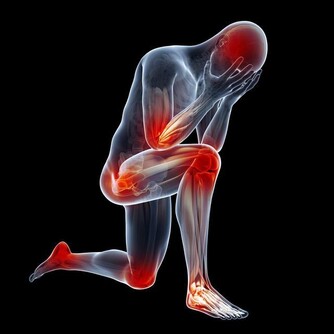

4、捏腳踝

腳踝分佈著淋巴管、血管、神經等重要組織,是腳部與人體血液流動的重要關口,流經靜脈回心血液。

當心臟不能好好工作時,靜脈血液不能順利回流,引起靜脈內壓力升高,體液漏出進入組織間隙,表現為下肢水腫,尤其是腳踝水腫症狀。

檢測方法是:手指按壓腳踝或小腿,手指鬆開後按壓部位呈凹陷狀,通常不能立即恢復。出現這種情況時,須及時就醫做下肢超聲檢查。

建議每天不妨抽點時間做做踝關節運動,以促進全身的血液循環,增加回心血量,保護心臟。具體方法是:

(1)站立旋踝,一腳站立,另一隻腳旋轉畫圈,雙腳交替進行,每次10分鐘左右。

(2)交替踮腳,兩腳腳尖前1/3腳掌著地,其餘2/3懸空站立,踮起腳尖,放下,重複20次。

需要注意的是,活動腳踝時切忌用力過大、過猛,以防踝關節軟組織損傷。